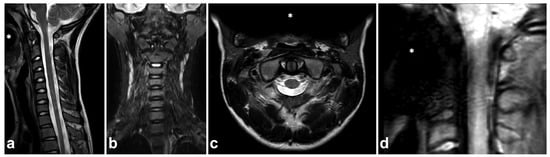

Figure 23.

(a) Sagittal T2-weighted. (b) Coronal STIR. (c) Axial T2-weighted. (d) Sagittal PD-weighted, dedicated small-FOV upper cervical spine series. A 12-year-old male, flexion and axial load to the cervical spine in a trampoline accident. The patient wears braces. Metal-induced artifacts (asterisks) are seen, but they disturb assessments of the spine only in small-FOV PD-weighted imaging.